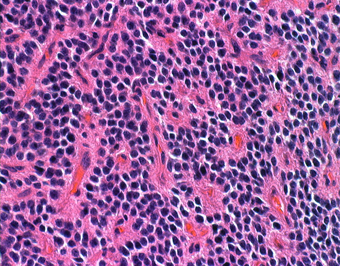

病理所見

石灰化(画面右側の紫色の部分)とともに、均一な大きさの円形の核を有する腫瘍細胞が敷石状に配列している。

核周囲は明るく抜けている。腫瘍細胞間には細い血管が介在し、腫瘍細胞を区画している。

腫瘍細胞間には好酸性(ピンク色)の細線維性基質が認められる。

免疫染色(Olig2)。HE染色で核周囲が明るく抜ける形態からoligodendrogliomaが鑑別となるが、Olig2は陰性で、oligodendrogliomaは否定される。

免疫染色(Synaotphysin:神経内分泌marker)。腫瘍細胞間の細線維性基質に陽性を示す。